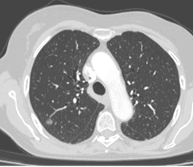

Reconstructions 3D

De quoi s’agit-il ?

Nous reconstruisons l’anatomie du patient en 3 dimensions grâce à un scanner thoracique (en utilisant le logiciel Synapse 3D) avant l’opération afin de la préparer car chaque patient est unique et chaque anatomie est différente.

A quoi ça sert ?

Les reconstructions 3D permettent au chirurgien de :

- diminuer la durée de l’intervention chirurgicale grâce à un gain de temps de dissection

- planifier le déroulé de l’intervention chirurgicale, c’est-à-dire , prévoir les étapes de dissection de l’organe

- réaliser des interventions plus complexes qu’auparavant grâce à une meilleure précision de la connaissance de l’anatomie du patient qui est soigné

- diminuer le risque d’erreur anatomique pendant l’opération quand les patients ont une anatomie inhabituelle

- diminuer le risque d’accident hémorragique lors de l’intervention

- améliorer les marges de résection de sécurité d’une tumeur en augmentant ainsi la qualité oncologique du geste